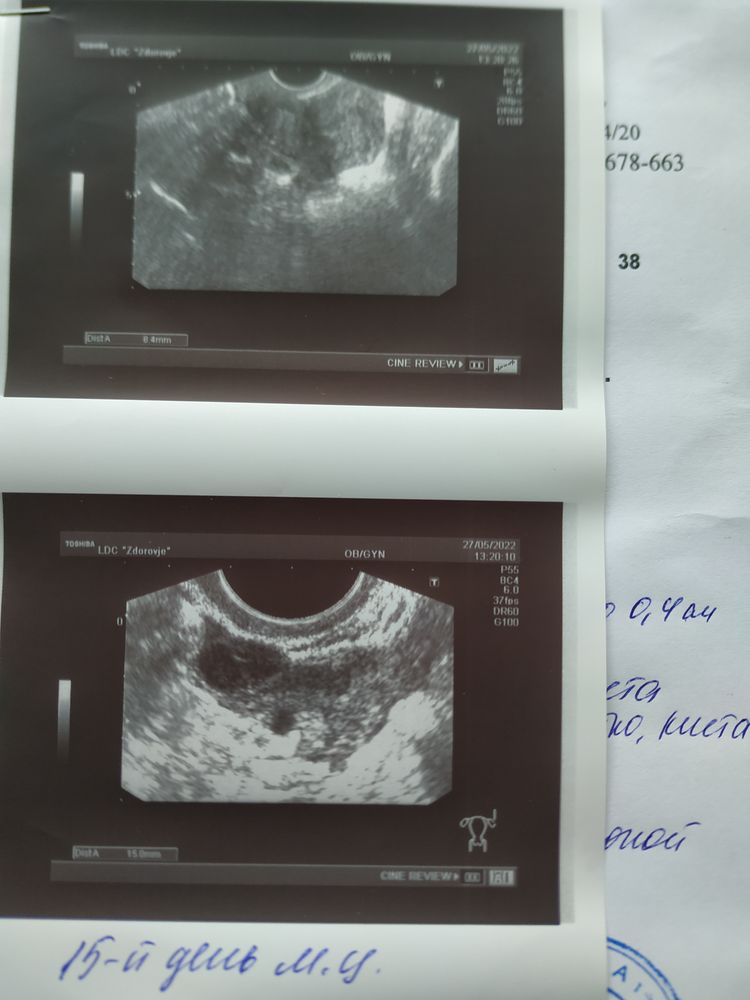

УЗИ от 27.05.22. Не все потеряно.

19 дпо. Полёт нормальный 1 дц..